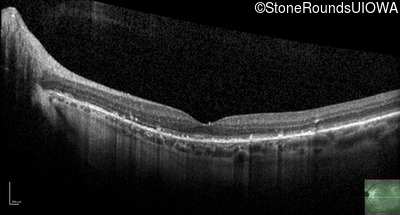

Optical Coherence Tomography - Left - 20/25 +3

Exemplar / OCT Stack

OCT Stack